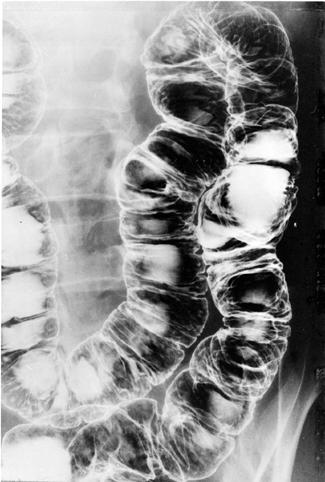

대장 전역에 미만성의 혈관이상(정맥괴 유사)을 나타낸 예

종양양 병변/미만성 정맥류

대장/2구역 이상의 대장에 걸치는 것

X-P